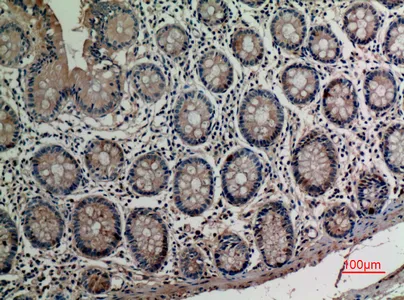

Adenosine A2A-R Rabbit Polyclonal Antibody

Cat: APRab06622

Size1:50μl Price1:$118

Size2:100μl Price2:$220

Size3:500μl Price3:$980

Size2:100μl Price2:$220

Size3:500μl Price3:$980